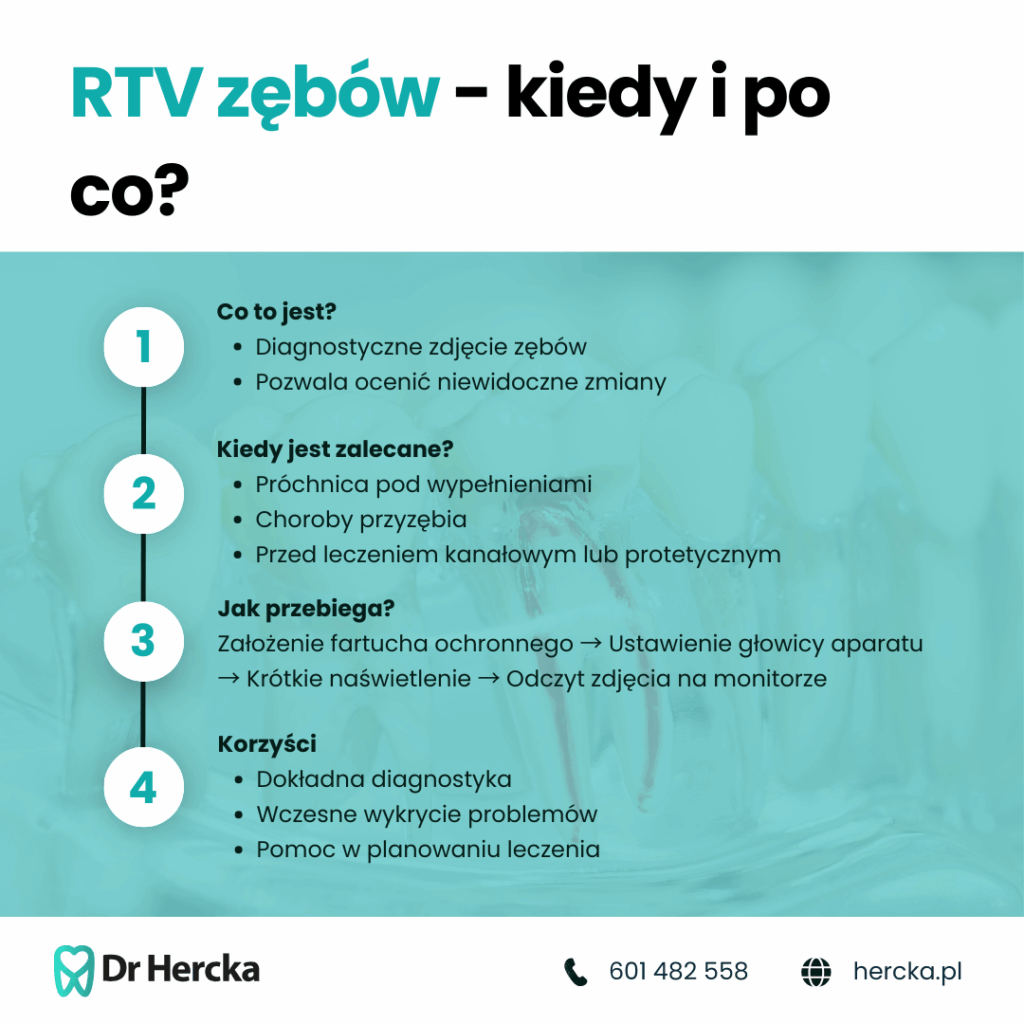

Wskazania do RTG zębów

Badanie RTG zębów jest nieodzownym elementem diagnostyki stomatologicznej, pomagającym w wykrywaniu schorzeń niewidocznych gołym okiem. Wskazaniami do jego wykonania mogą być zarówno rutynowe kontrole, jak i konkretne problemy zdrowotne. Poniżej podajemy przykłady, kiedy stosowane jest RTG zębów.

1. Diagnostyka próchnicy i chorób miazgi

Zdjęcia rentgenowskie pozwalają wykryć ubytki w trudno dostępnych miejscach, takich jak przestrzenie międzyzębowe czy okolice pod wypełnieniami. RTG jest także kluczowe w ocenie stanu miazgi zębowej oraz ewentualnych stanów zapalnych.

2. Planowanie i kontrola leczenia kanałowego

Leczenie endodontyczne wymaga precyzyjnej diagnostyki – RTG umożliwia ocenę długości i kształtu kanałów korzeniowych, a także weryfikację skuteczności przeprowadzonego zabiegu.

6. Diagnostyka chorób przyzębia

W przypadkach zaawansowanej paradontozy RTG pozwala określić stopień zaniku kości i monitorować efektywność leczenia. Jest to szczególnie ważne u pacjentów z przewlekłymi chorobami dziąseł.

Jak przebiega RTG zębów?

Badanie RTG zębów jest szybkie, bezbolesne i nie wymaga specjalnego przygotowania. Cała procedura trwa zaledwie kilka minut i pozwala uzyskać precyzyjny obraz struktur kostnych jamy ustnej.

1. Przygotowanie do badania

Przed rozpoczęciem prześwietlenia pacjent proszony jest o zdjęcie metalowych elementów znajdujących się w okolicy głowy i szyi, takich jak kolczyki, okulary czy protezy ruchome, które mogłyby zakłócić obraz. W celu ochrony przed promieniowaniem zakłada się także specjalny fartuch ołowiany.

2. Wykonanie zdjęcia RTG

W zależności od rodzaju badania, RTG może być wykonywane na trzy sposoby:

- RTG punktowe – wykorzystywane do oceny pojedynczych zębów, polega na umieszczeniu niewielkiego czujnika wewnątrz jamy ustnej, przy jednoczesnym naświetleniu obszaru zębowego z zewnątrz.

- RTG pantomograficzne (panoramiczne) – pacjent staje nieruchomo, opierając brodę na specjalnym podparciu, a aparat wykonuje pełny obrót wokół jego głowy, rejestrując obraz całej szczęki i żuchwy.

- RTG cefalometryczne – stosowane w ortodoncji, pokazuje czaszkę z profilu i pozwala na ocenę wzajemnego położenia kości twarzoczaszki.

3. Analiza wyników

Obraz RTG jest gotowy niemal natychmiast i może być wyświetlony na ekranie komputera. Stomatolog ocenia stan zębów, korzeni i otaczających tkanek, a następnie omawia wyniki z pacjentem. Jeśli konieczne jest dalsze leczenie, RTG pozwala precyzyjnie zaplanować kolejne kroki.

RTG zębów – czy warto?

RTG zębów to jedno z najważniejszych badań diagnostycznych w stomatologii. Pozwala ono wykrywać zmiany niewidoczne podczas standardowego badania jamy ustnej, umożliwiając szybkie i skuteczne leczenie. Czy warto je wykonywać? Zdecydowanie tak – oto najważniejsze powody.

1. Wczesne wykrywanie problemów

RTG pozwala na diagnostykę próchnicy, infekcji, torbieli, złamań oraz chorób przyzębia na bardzo wczesnym etapie. Dzięki temu można uniknąć poważniejszych problemów, takich jak rozległe ubytki, konieczność leczenia kanałowego czy nawet utrata zęba.